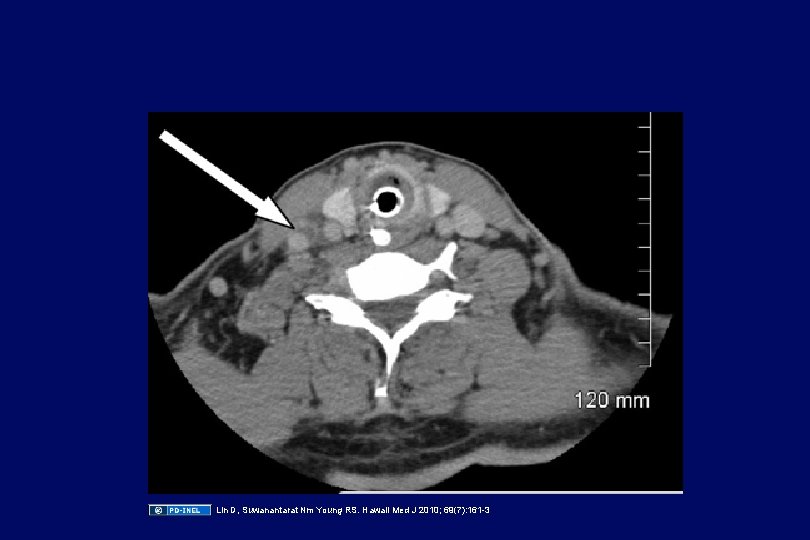

Case: neck and chest pain • A 22 year old male who recently had an prolonged episode of pharyngitis now presents with high fever, and exquisite pain, tenderness and swelling of his left neck for 2 days. • This morning, he developed sharp pain in the left lower chest with deep breathing • A blood culture is positive for an anaerobe

Lin D, Suwanantarat Nm Young RS. Hawaii Med J 2010; 69(7): 161 -3

Lin D, Suwanantarat Nm Young RS. Hawaii Med J 2010; 69(7): 161 -3

Lemierre’s syndrome • Or “post-anginal sepsis” (very rare) • Occurs after prolonged or severe pharyngitis • Septic thrombophlebitis with Fusobacterium necrophorum (probably from the mouth) associated with septic pulmonary emboli to the lungs